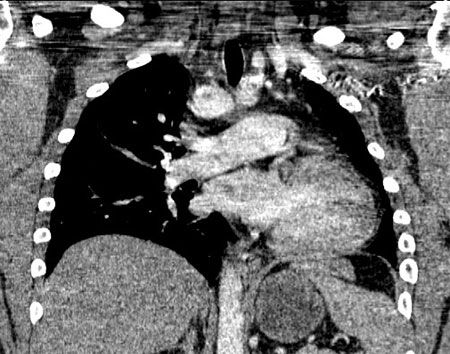

An ECG showed no significant abnormalities. A prominent right pulmonary artery, a right-sided aortic arch, cardiomegaly, and diminished left lung volumes were seen on a chest radiograph (Figure 1). An echocardiogram demonstrated normal chambers with no systolic dysfunction, no evidence of valvular or congenital heart disease, and normal pulmonary artery pressures. CT angiograms (CTAs) of the chest (Figures 2 and 3), a cardiac MRI scan (Figure 4), and a ventilation-perfusion (V/Q) lung scan (Figure 5) were also obtained. Pulmonary function tests (PFTs) revealed a moderate restrictive pattern (total lung capacity, 68% of predicted) with a mildly decreased carbon monoxide-diffusing capacity (76% of predicted) as per the ATS/ ERS task force (2005) standardization guidelines.

The CTAs showed complete absence of the left pulmonary artery, an enlarged right pulmonary artery, and a hypoplastic left lung (Figures 2 and 3). Isolated complete absence of the left pulmonary artery, an enlarged right pulmonary artery, a hypoplastic left lung, and a right-sided aorta were seen on the cardiac MRI scan (Figure 4). The V/Q lung scan showed hypoventilation of the left lung, with complete absence of left lung perfusion (Figure 5). These findings confirmed the diagnosis of isolated unilateral absence of pulmonary artery (UAPA).